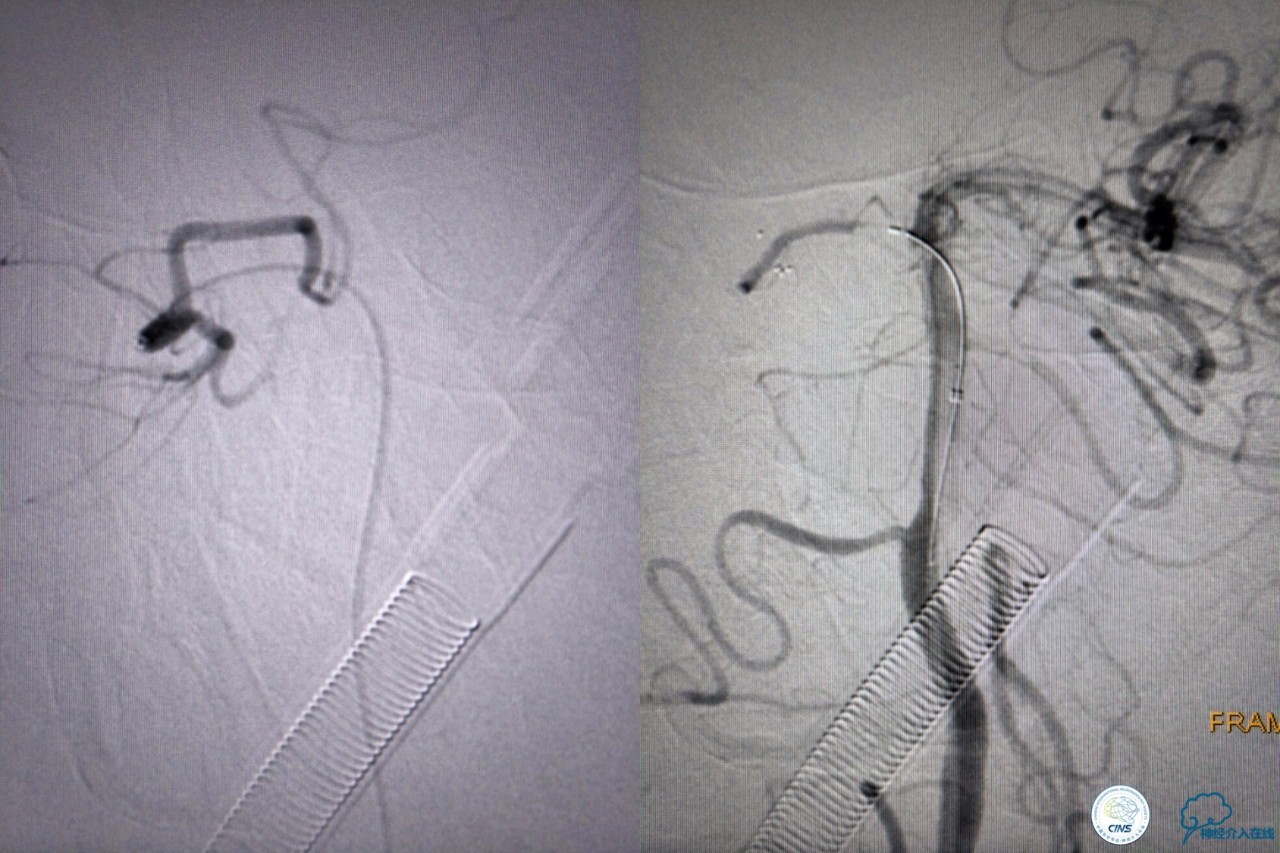

第三次取栓,支架放入左侧大脑后取栓。

第三次取栓后,左侧大脑后动脉开通,但是栓子再次栓塞右侧大脑后动脉,血栓在基地动脉顶端来回左右摆动,下一次,怎办?血栓负荷太多,可以使用solumbar技术,可以没有颅内导管,没办法,换用更大的支架6-20mm,但费用增加不少,与家属沟通后同意使用,第四次取栓:

血栓负荷还是很大,左侧大脑后再通,但右侧大脑后又闭塞,只能第五次取栓,支架放到右侧大脑后动脉更远。

好大的血栓,支架释放后,血管无复流,拉一把!